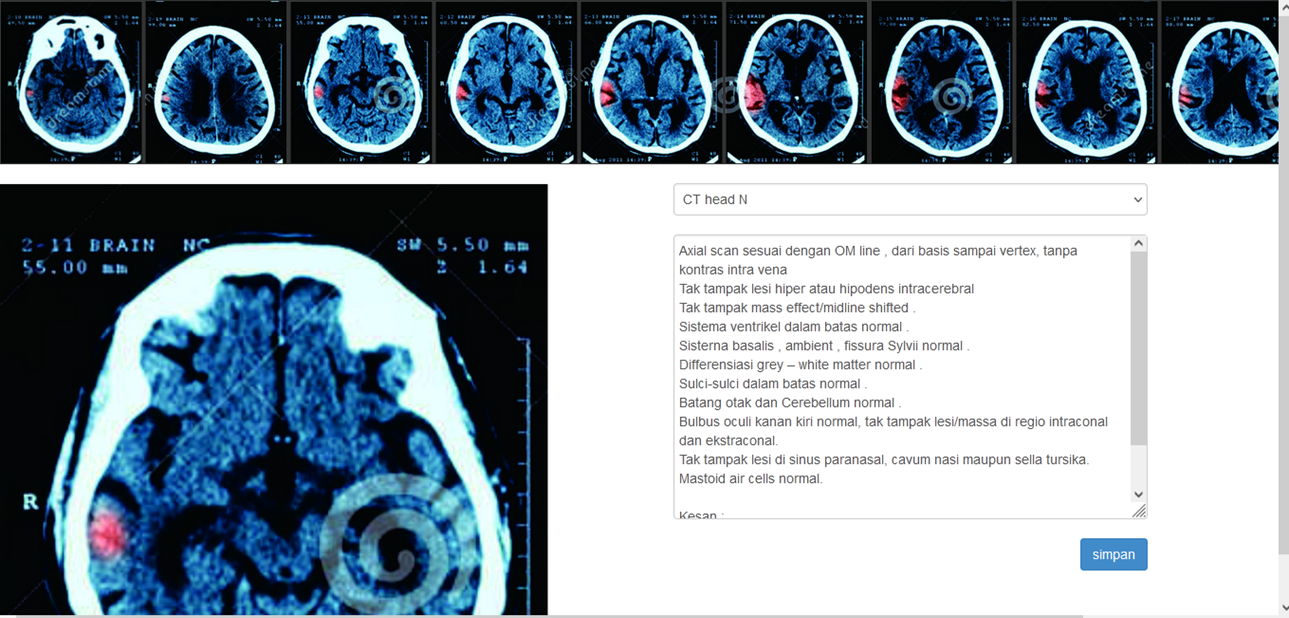

RADIANT Radiology Intelligence Analyser System

Enigmed Radiant is special complex radiology system that will give you advice,prediction,control and total analysing result with laboratory result Our artifisual intelligence will analyse and give advice the situation realtime